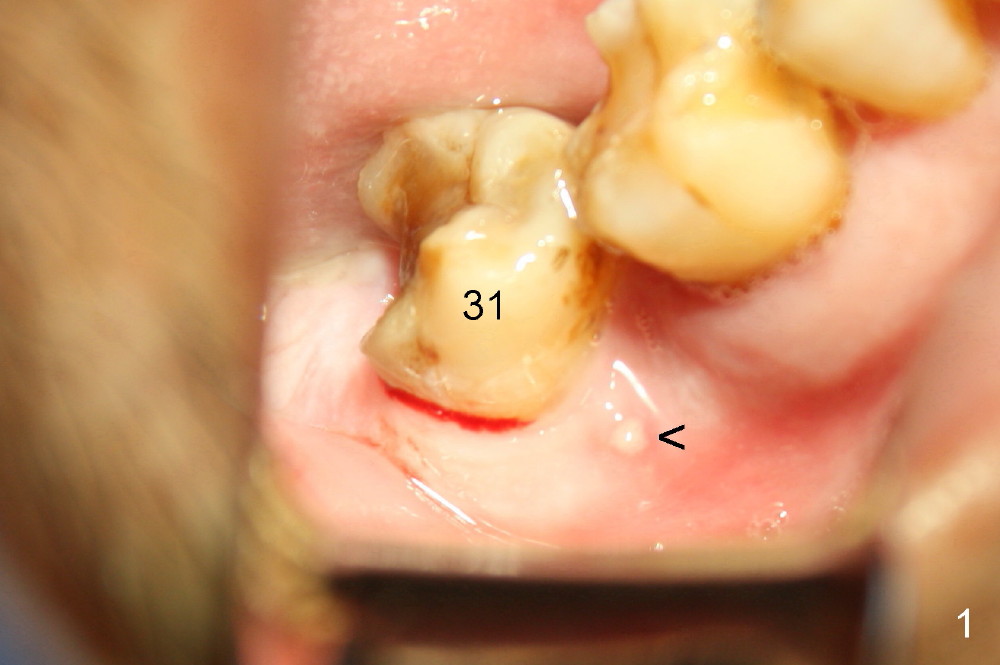

A 52-year-old man (heavy smoker) presents to office without schedule.  He has severe pain at #31 and wants extraction immediately (Fig.1,2).  He likes the idea of immediate implant, but we do not have time for it that day.  Therefore the tooth is extracted (Fig.3).  The socket is single.  After debridement, bone graft (Fig.5 *) and collagen membrane (Fig.4) are placed.

To prevent nerve injury, a PA should be taken prior to implant placement, preferably using sensor 2.  If bone density in the socket increases, a shorter implant can be used.  Prepare implant positioners, which will be used to determine whether a tissue punch will remove too much keratinized gingiva or not.  If the gingiva over the original socket is thin, #15 scalpel will be used to make a short mesiodistal straight incision (~10 mm for 6 mm diameter implant for example).  Most importantly, try not to use drills.  If there is need to use them, confine the drills within the original socket.  It is possible to use taps to finish osteotomy (1, 2).